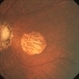

- Inferonasal Branch Retinal Vein Occlusion

- Noemí Hernández, Asociación para Evitar la Ceguera en México

- Fundus of a 55 year-old male showing intraretinal hemorrhages in the inferonasal quadrant.